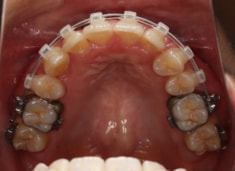

治療前